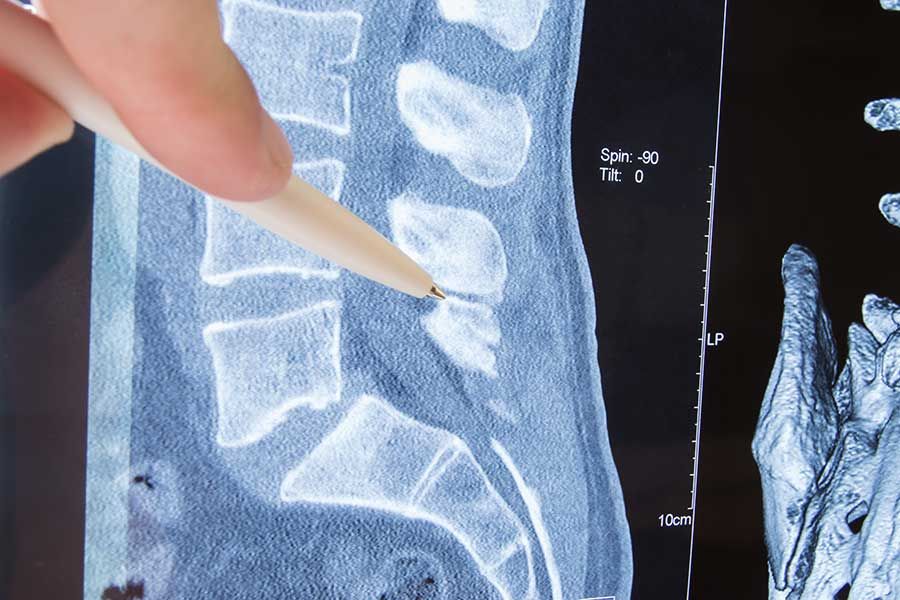

Magnetic resonance imaging (MRI) is another modern diagnostic imaging technique that produces cross-sectional images of your body. MRI works without radiation using magnetic fields and a sophisticated computer to take high-resolution pictures of your bones and soft tissues. During the painless procedure, you lie as motionless as possible on a table that slides into the tube-shaped MRI scanner. The MRI creates a magnetic field around you and then pulses radio waves to the area of your body to be pictured. The radio waves cause your tissues to resonate. A computer records the rate at which your body’s various parts (tendons, ligaments, nerves, etc.) give off these vibrations, and translates the data into a detailed, two-dimensional picture. An MRI may help your doctor to diagnose your torn knee ligaments and cartilage, torn rotator cuffs, herniated disks, hip and pelvic problems, and other problems. An MRI may take 30 to 90 minutes.